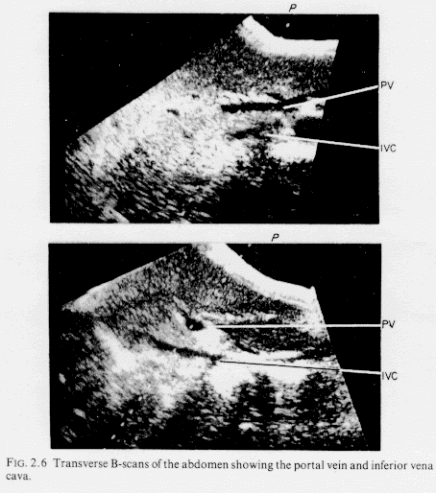

A major disadvantage of the simple continuous-wave flowmeter is its inability to discriminate in range. The continuous-wave transmission creates an ultrasonic beam which occupies the complete diffraction pattern of the transducer. Any target moving within this beam will contribute to the final Doppler output. During clinical use of CW devices this sometimes makes it impossible to isolate flow in adjoining blood vessels. For example, in the B-scan tomograms of the abdomen shown in Fig. 2.6, a continuous-wave flowmeter transducer situated at P and interrogating flow in the portal vein (PV) would also receive interfering signals from the more distant inferior vena cava (IVC). Range selectivity can sometimes be a vital requirement in Doppler investigations and so this section describes the various methods of coding the transmitted burst and processing the received echo so that the range of the moving targets can be determined. During the description the effects on the basic Doppler equation of imposing restraints on the axial selectivity of the flowmeter will be investigated.